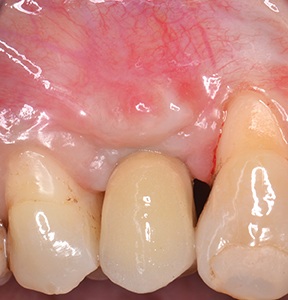

At the end of the osseointegration period, the implant was uncovered and the healing abutment placed. Following soft-tissue conditioning by means of a provisional crown (Fig. 26), a metal-ceramic crown was cemented onto the prosthetic abutment (Fig. 27).

Fig. 26: Soft-tissue conditioning with a provisional crown

Fig. 27: Final metal-ceramic crown cemented onto the prosthetic abutment